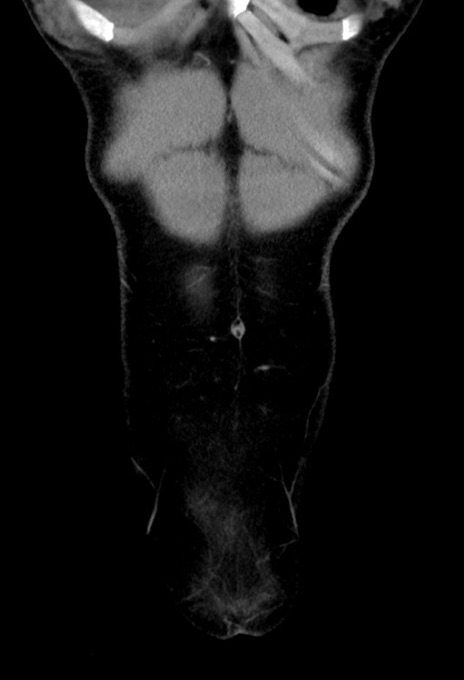

症例17(冠状断像)

【症例】20歳代女性

【主訴】嘔吐、下腹部痛

【現病歴】昨日夕食後に嘔吐し下腹部痛が出現。本日になっても嘔吐持続し改善しないため来院。

【身体所見】意識清明、BT 37.2℃、BP 108/67mmHg、腹部:平坦、やや硬、下腹部正中から右にかけて圧痛あり、反跳痛軽度あり、tapping pain(+)。

【データ】WBC 13600、CRP 14.94